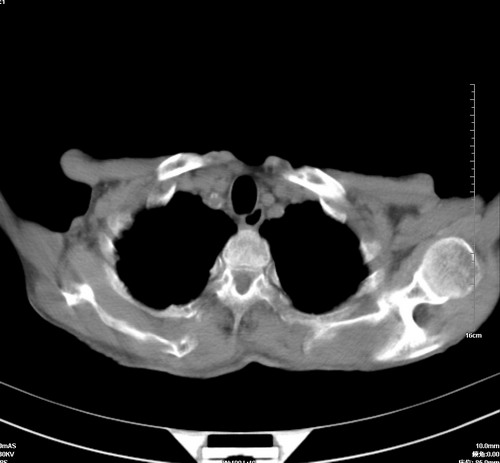

病人,女,79岁,主要因腹疼二月入院,彩超,肝,胆,脾,未见异常,胸透上消化道造影未见异常,化验白细胞增高,内科医生让做胸部ct检查,因为熟人多做了腹部(外科会诊考虑胆囊炎).现ct片如下请假各位战友.

中后纵隔占位,气管、食道受压、变形、移位。恶性可能性大。

考虑:中后纵隔转移瘤可能性大,主动脉硬化。

1 气管旁、隆突下淋巴结明显肿大,肝左叶外侧段低密影,都考虑转移。

后中纵隔团块影,伴气管、食道受压移位,首先考虑转移瘤,肝s5段低密度灶。建议增强检查,另外其结肠是否有问题请提供,右肺部分肺叶局限含气增多,考虑局限肺气肿。

建议强化检查,考虑纵隔型肺癌,小细胞可能性大。